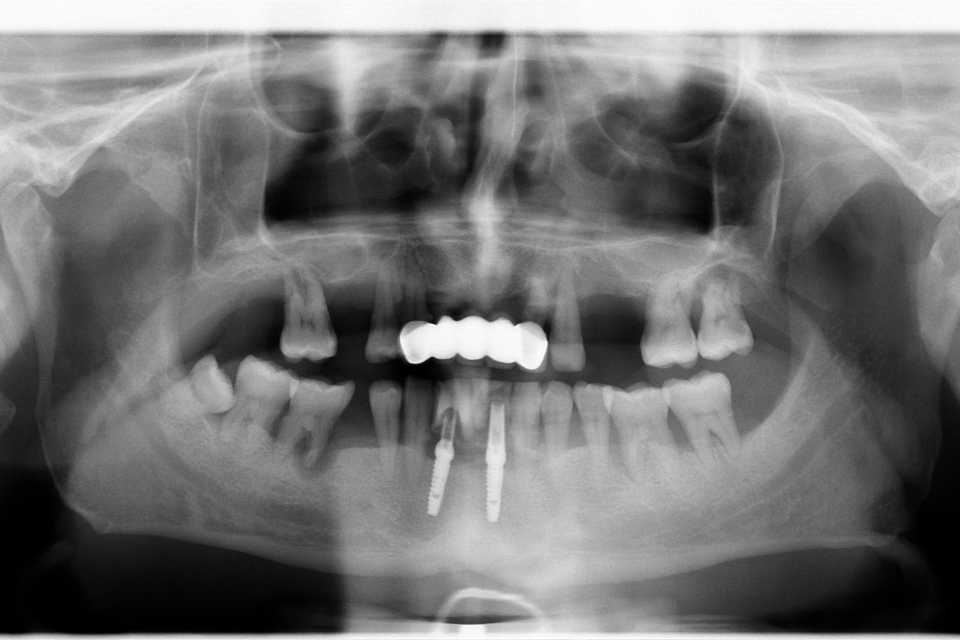

Pacient în vârstă de 39 de ani se prezintă în clinica noastră cu probleme de natură estetică și funcțională la nivelul maxilarului.

În urma consultului de specialitate, s-a decis extracția dinților parodontotici și a unei lucrări vechi, urmată de inserarea a 7 implanturi dentare Mega-Gen AnyRidge, cu adiții osoase și sinus lift bilateral. Implanturile au fost poziționate strategic pentru a permite o reabilitare protetică completă, formată din 14 dinți, asigurând astfel zâmbetul dorit de pacient.